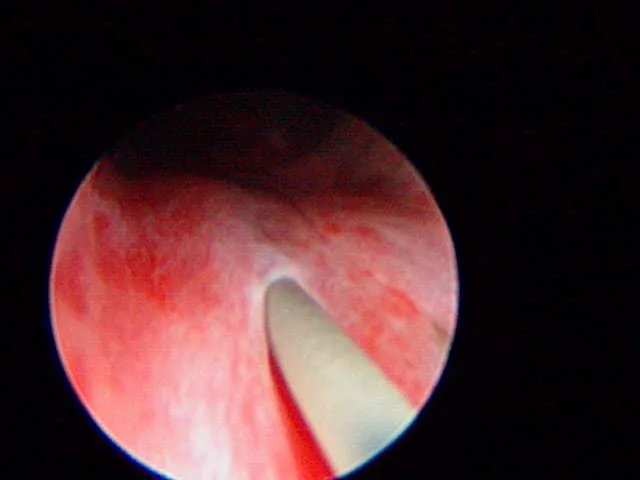

Urinary Endoscopy

An experienced endoscopist can usually identify EUs (Figure 3, arrows; U = urethra lumen).

(Photo courtesy of Dr. John Kruger, Michigan State University)